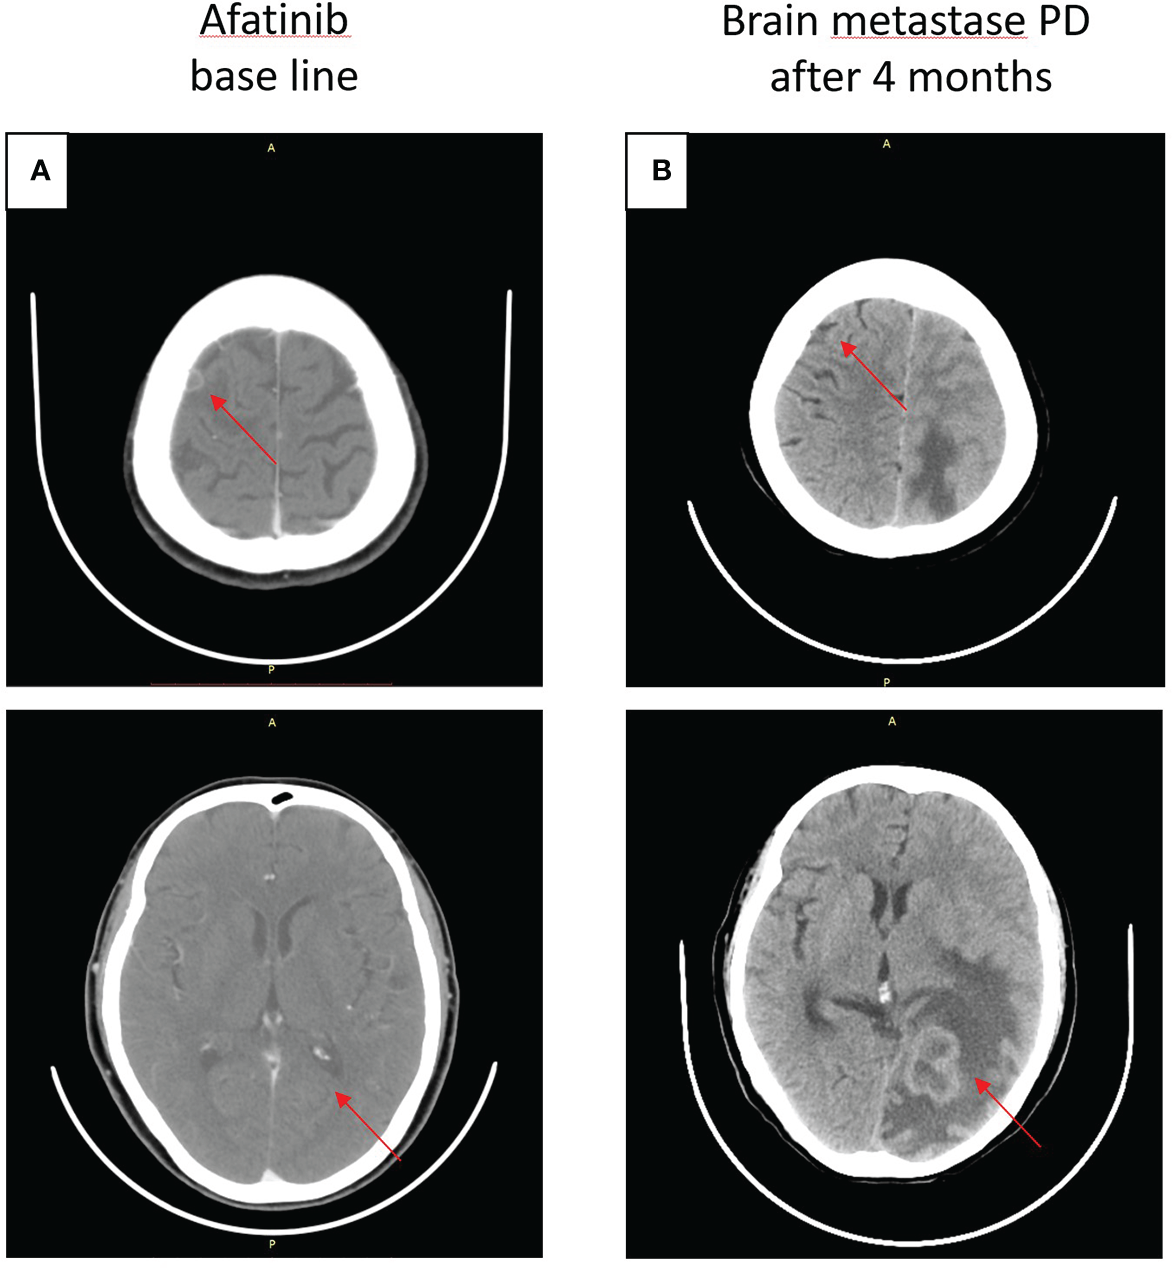

On 14 July 2020, a CT scan was taken after the seizure of the patient, and the result revealed brain metastases (BMS) in the right frontal lobe of the brain, and then she accepted brain radiotherapy, which started from 20 July 2020, with a dose of 500 cGy/f, once a day, five times a week, and a planned target volume tumor absorbed dose (PTV DT) was 5000 cGy/10f. Subsequently, the patient started oral afatinib 40 mg daily as first-line therapy on 4 August 2020 (Figure 2A), and achieved stable disease for 7 months until January 2021 (Figure 2B).

Figure 2

Craniocerebral CT about clinical response to afatinib therapy at different times. (A) Baseline before afatinib treatment. (B) Brain metastases progressive disease (PD) after 4 months.